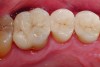

Fig 5. Situation after removal of the failing restorations. Recurrent caries involved proximal areas, leading to extensive proximal cavities. The remaining enamel is very thin or even absent along the cervical margins. A direct approach is not indicated due to cavity dimensions, margin position, and dentin quality.